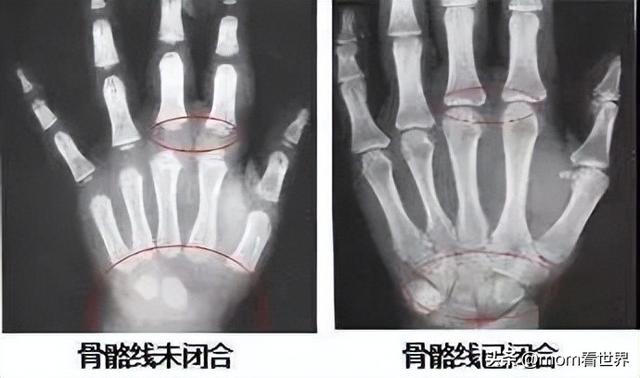

孩子最终能长多高是由骨骺线决定的。

什么是骨骺呢?

孩子在婴幼儿时期,长骨的骨干和骨骺之间,存在一个软骨带。在X线片中,显示为分离间隙,这个间隙正是为骨骼伸长预留的空间。

青春期结束后,这个软骨带将钙化成一段白线,也叫“成长线”,标志着骨干和骨骺彻底融合,长骨伸长结束,孩子的个子也就不会再长高了。

下面这张图,可以简单地让我们了解什么叫骨骺闭合。

骨骺未闭合前,孩子还能继续生长;若骨骺闭合,孩子就会停止生长。

而骨龄检查就是拍摄手腕部的 X 光片,观察左手(一般拍左手,少数拍右手)掌指骨,腕骨以及桡尺骨的骨化中心的发育程度。

骨龄小就意味着距离骨骺闭合的时间还长,而骨龄大则意味着距离骨骺闭合的时间比较短了。